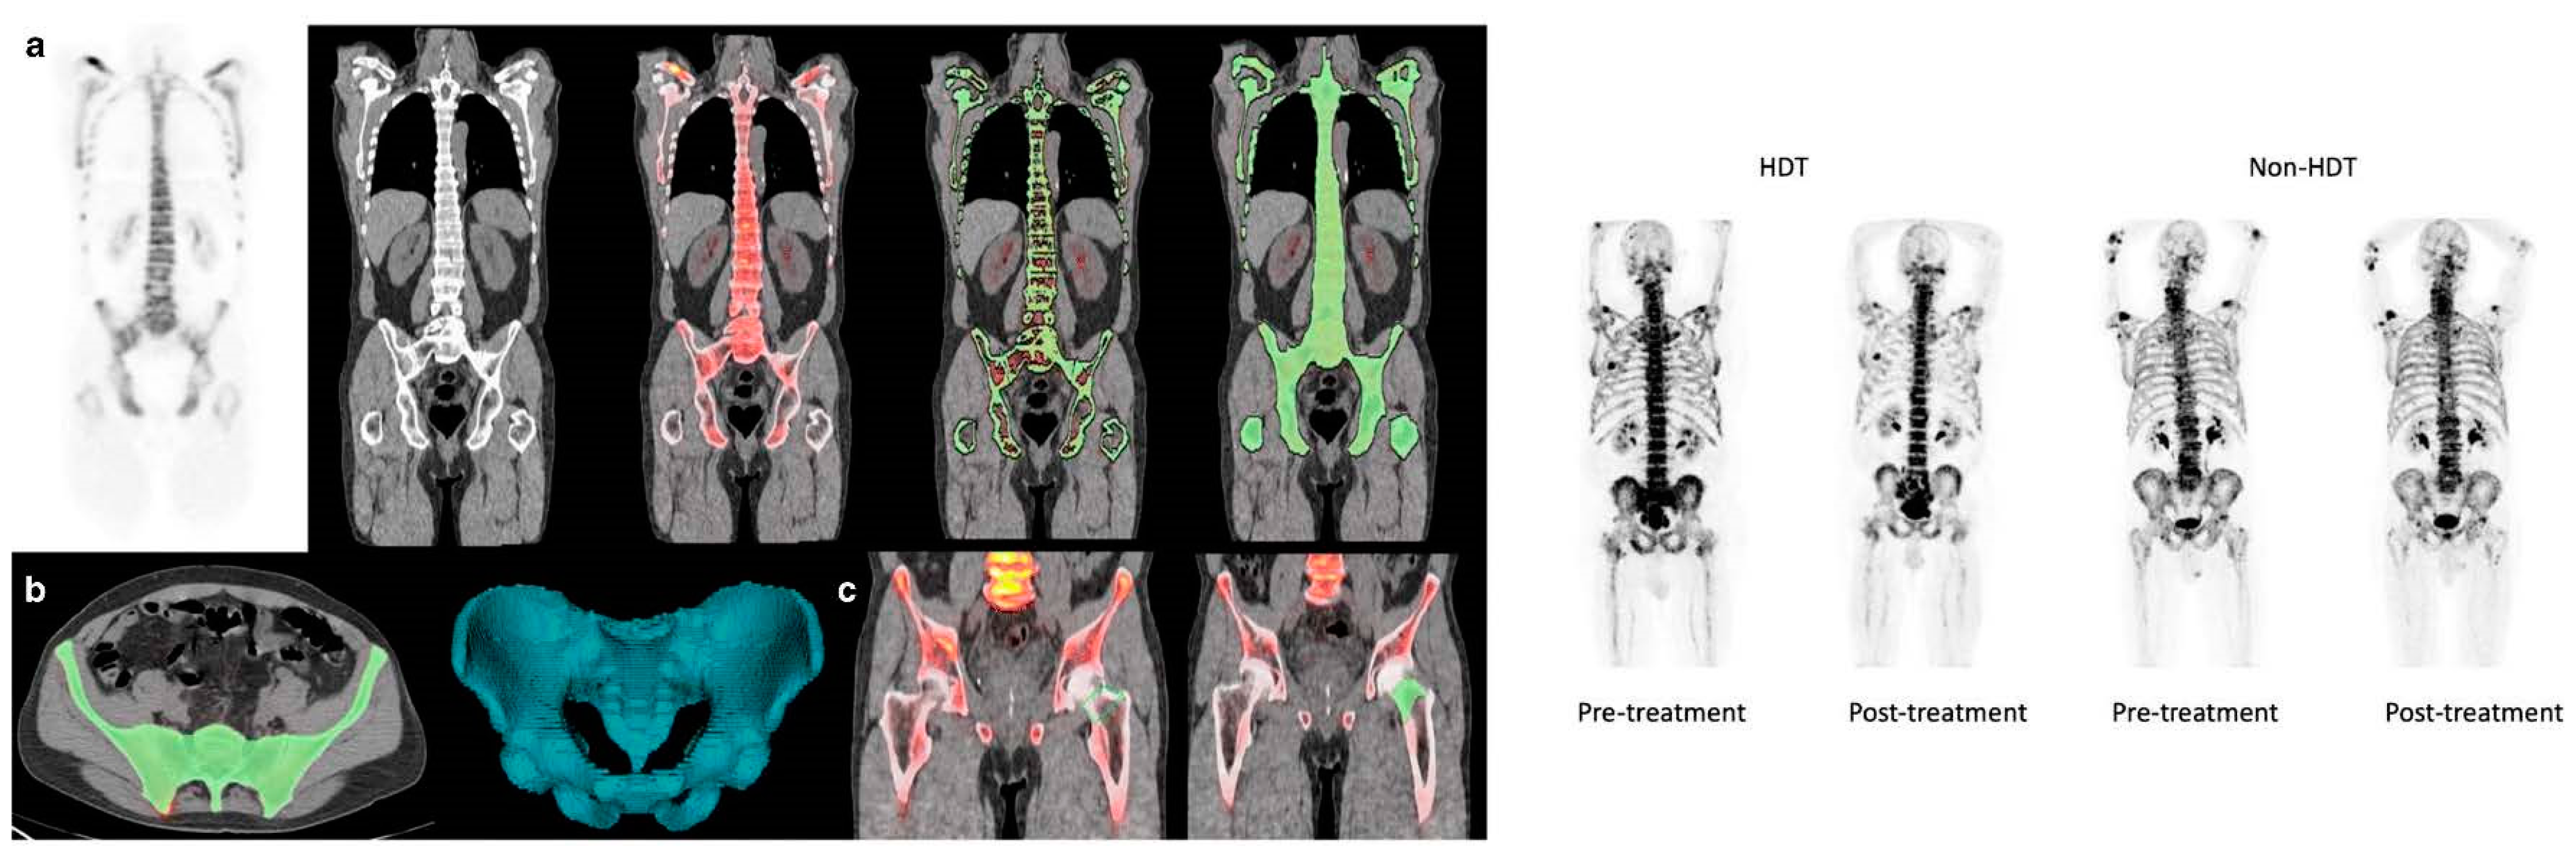

4. Importance of [18F]FDG PET/CT in Assessing Treatment Efficacy

4.2. Assessment of Myeloma Patients after Treatment

- Zirakchian Zadeh, M.; Østergaard, B.; Raynor, W.Y.; Revheim, M.E.; Seraj, S.M.; Acosta-Montenegro, O.; Ayubcha, C.; Yellanki, D.P.; Al-Zaghal, A.; Nielsen, A.L.; et al. Comparison of 18F-sodium fluoride uptake in the whole bone, pelvis, and femoral neck of multiple myeloma patients before and after high-dose therapy and conventional-dose chemotherapy. Eur. J. Nucl. Med. Mol. Imaging 2020, 47, 2846–2855. [Google Scholar] [CrossRef] [PubMed]